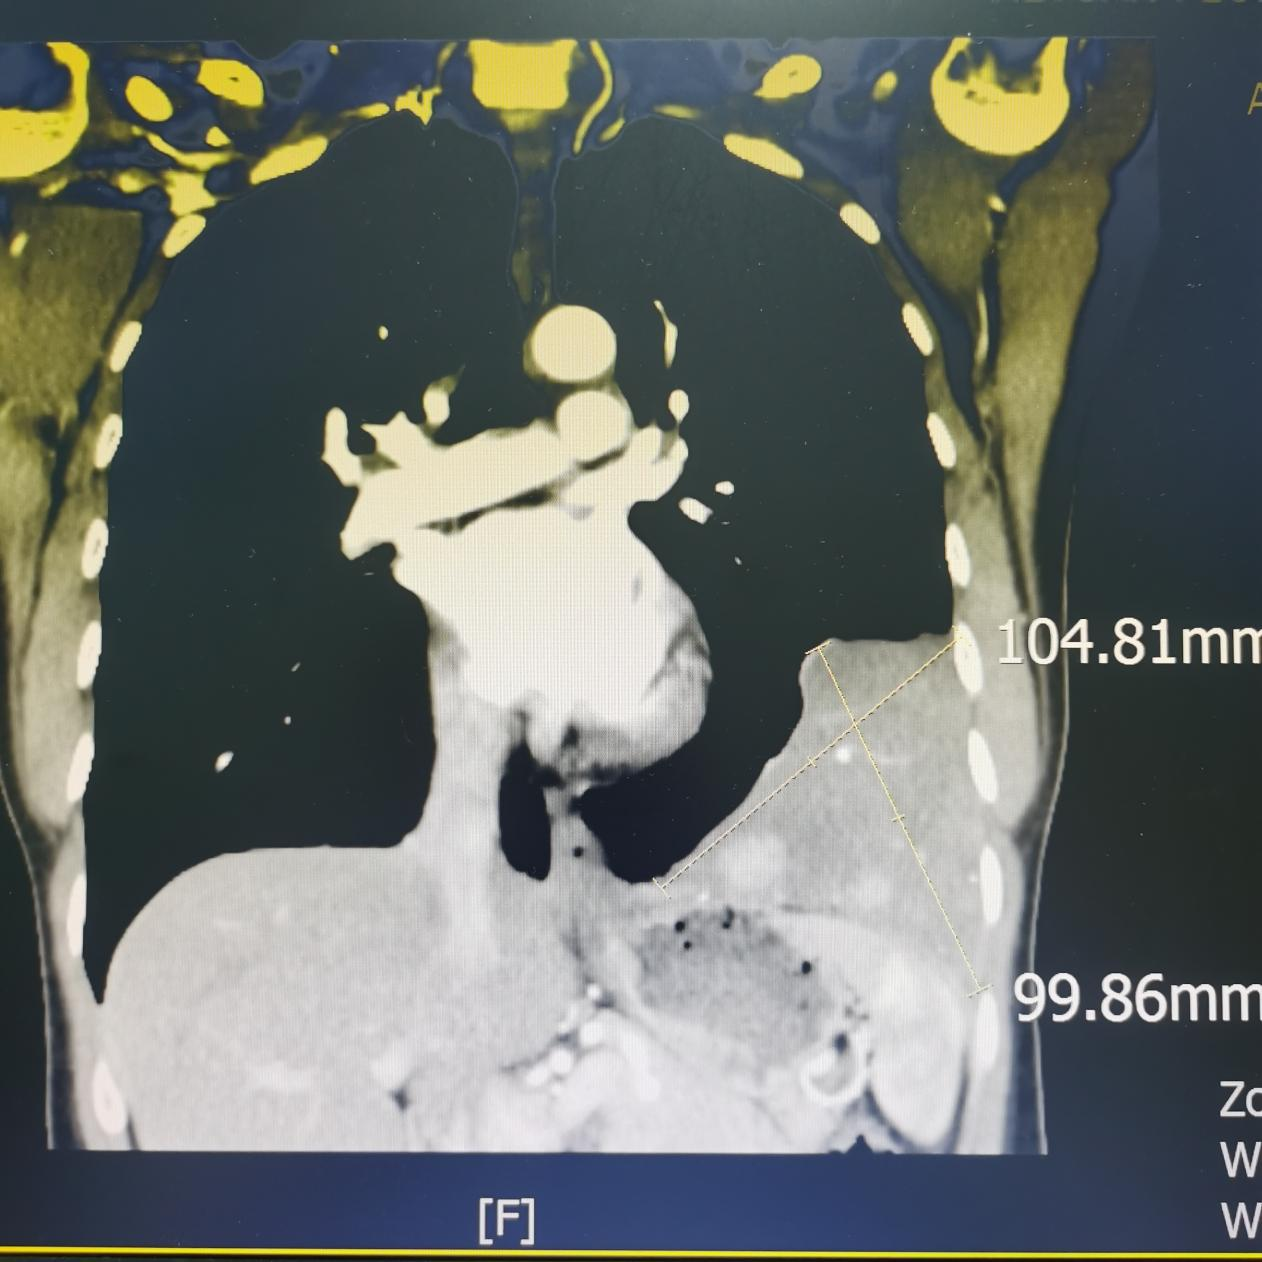

患者入院后,进一步完善胸部增强CT扫描,结果示:左侧胸腔见团块状高密度影影,范围大小约146mm×64mm×101mm,与邻近胸膜呈宽基底连接,边界不清,其内密度不均,增强扫描动脉期见呈结节、斑片状明显强化,大结节内可见斑片状无强化区,部分病变未见强化,病变内可见增粗、迂曲强化;静脉期病变强化范围较前片增多、增大,呈持续性明显强化,大结节呈填充强化,中央低密度未见强化;邻近左肺可见斑片状高密度影,增强扫描呈明显强化。提示:左侧胸腔占位,考虑起源胸膜,以胸膜孤立性纤维肿瘤可能性大。同时完善胸部增强磁共振扫描(磁共振对软组织病变分辨率更优),同样考虑胸膜来源孤立性纤维肿瘤可能性大。

胸部磁共振增强提示左胸腔巨大占位